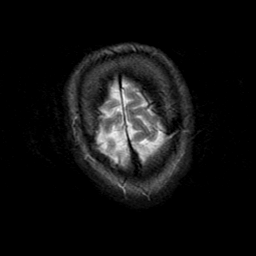

Subacute Stroke, overlay -- Slice #24

[Home][Help][Clinical] Slice 24

Click on sagittal image to select slice. Click on thin tickmark to change timepoint, or thick tickmark for overlay.

Keith A. Johnson (keith@bwh.harvard.edu), J. Alex Becker (jabecker@mit.edu)